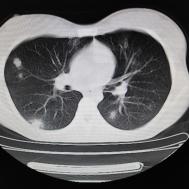

支原体肺炎1例CT影像表现

性别:女,年龄:26岁,低热,轻微胸痛,支原体阳性

两肺内及胸膜下多发斑片状高密度影,部分病灶密度较淡,部分实变,边缘可见渗出改变。

支原体肺炎是由支原体引起的以间质改变为主的肺炎。实验室检查支原体抗体呈阳性。支原体侵入肺内可引起支气管、细支气管黏膜及其周围间质充血、水肿,多核细胞浸润,侵入肺泡可产生肺泡浆液性渗出性炎症。CT早期主要改变为肺间质炎症,病变区肺纹理增粗而模糊,病变范围广泛,常累及多个肺叶,单侧或双侧的磨玻璃影及实变影,以双肺下叶多见,多呈小叶性分布。同时,患者的临床症状与CT改变不匹配,即临床症状明显好转或消失但肺部阴影吸收不明显。鉴别诊断:支气管肺炎好发于两中下肺的内、中带,病灶沿支气管分布,呈多发散在小的斑片状影,常合并阻塞性小叶性肺气肿或小叶性肺不张,结合临床多见于婴幼儿或年老体弱者。渗出浸润为主的继发性肺结核病灶表现为结节状或呈不规则斑片状影,边缘较模糊,密度不均匀,病灶内可见小空洞。增殖性病灶密度较高,边缘清楚,病灶内或周围可见不规则钙化灶。浸润性病变常与纤维化并存,可伴有邻近支气管扩张。结核分枝杆菌检查阳性。